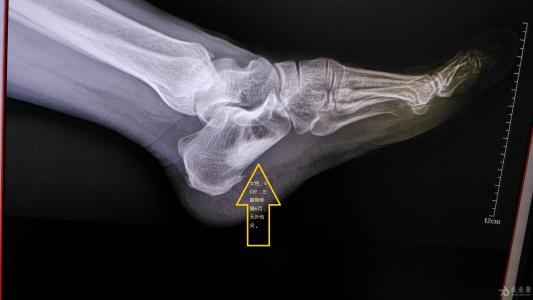

一、疼痛

【经络|身体这位六大信号,你要小心经络不通了】莫名的疼痛 , 可能是经络不通的表现 , 中医讲痛则不通、通则不痛 , 经络不通第一个感觉往往就是疼痛 , “初病在轻、久病久痛在络” 。